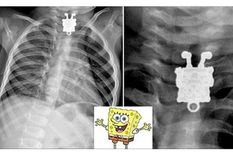

Un bebe se tragó un collar de Bob Esponja

radiografías

Las radiografías más insólitas y sus historias detrás